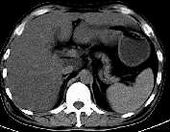

58岁男性患者,消瘦后体重锐减30斤,黄疸一周,谷胺酰胺转氨酶超过正常值20倍

肝脏肿大,上下达24层;肝脏平扫ct值约32hu(尾叶附近低密度灶ct值为4~10hu,而静脉期和延迟期其值19~24hu)。

平扫:肝脏体积增大,密度明显低与脾脏,肝尾叶见一类圆形低密度病灶,并向肝外突出于,大小?边界较模糊,ct值4-10hu(花省伞朋友说的)。肝门增大,似有一肿块。肝内胆管未见扩张,脾不大,密度均匀。